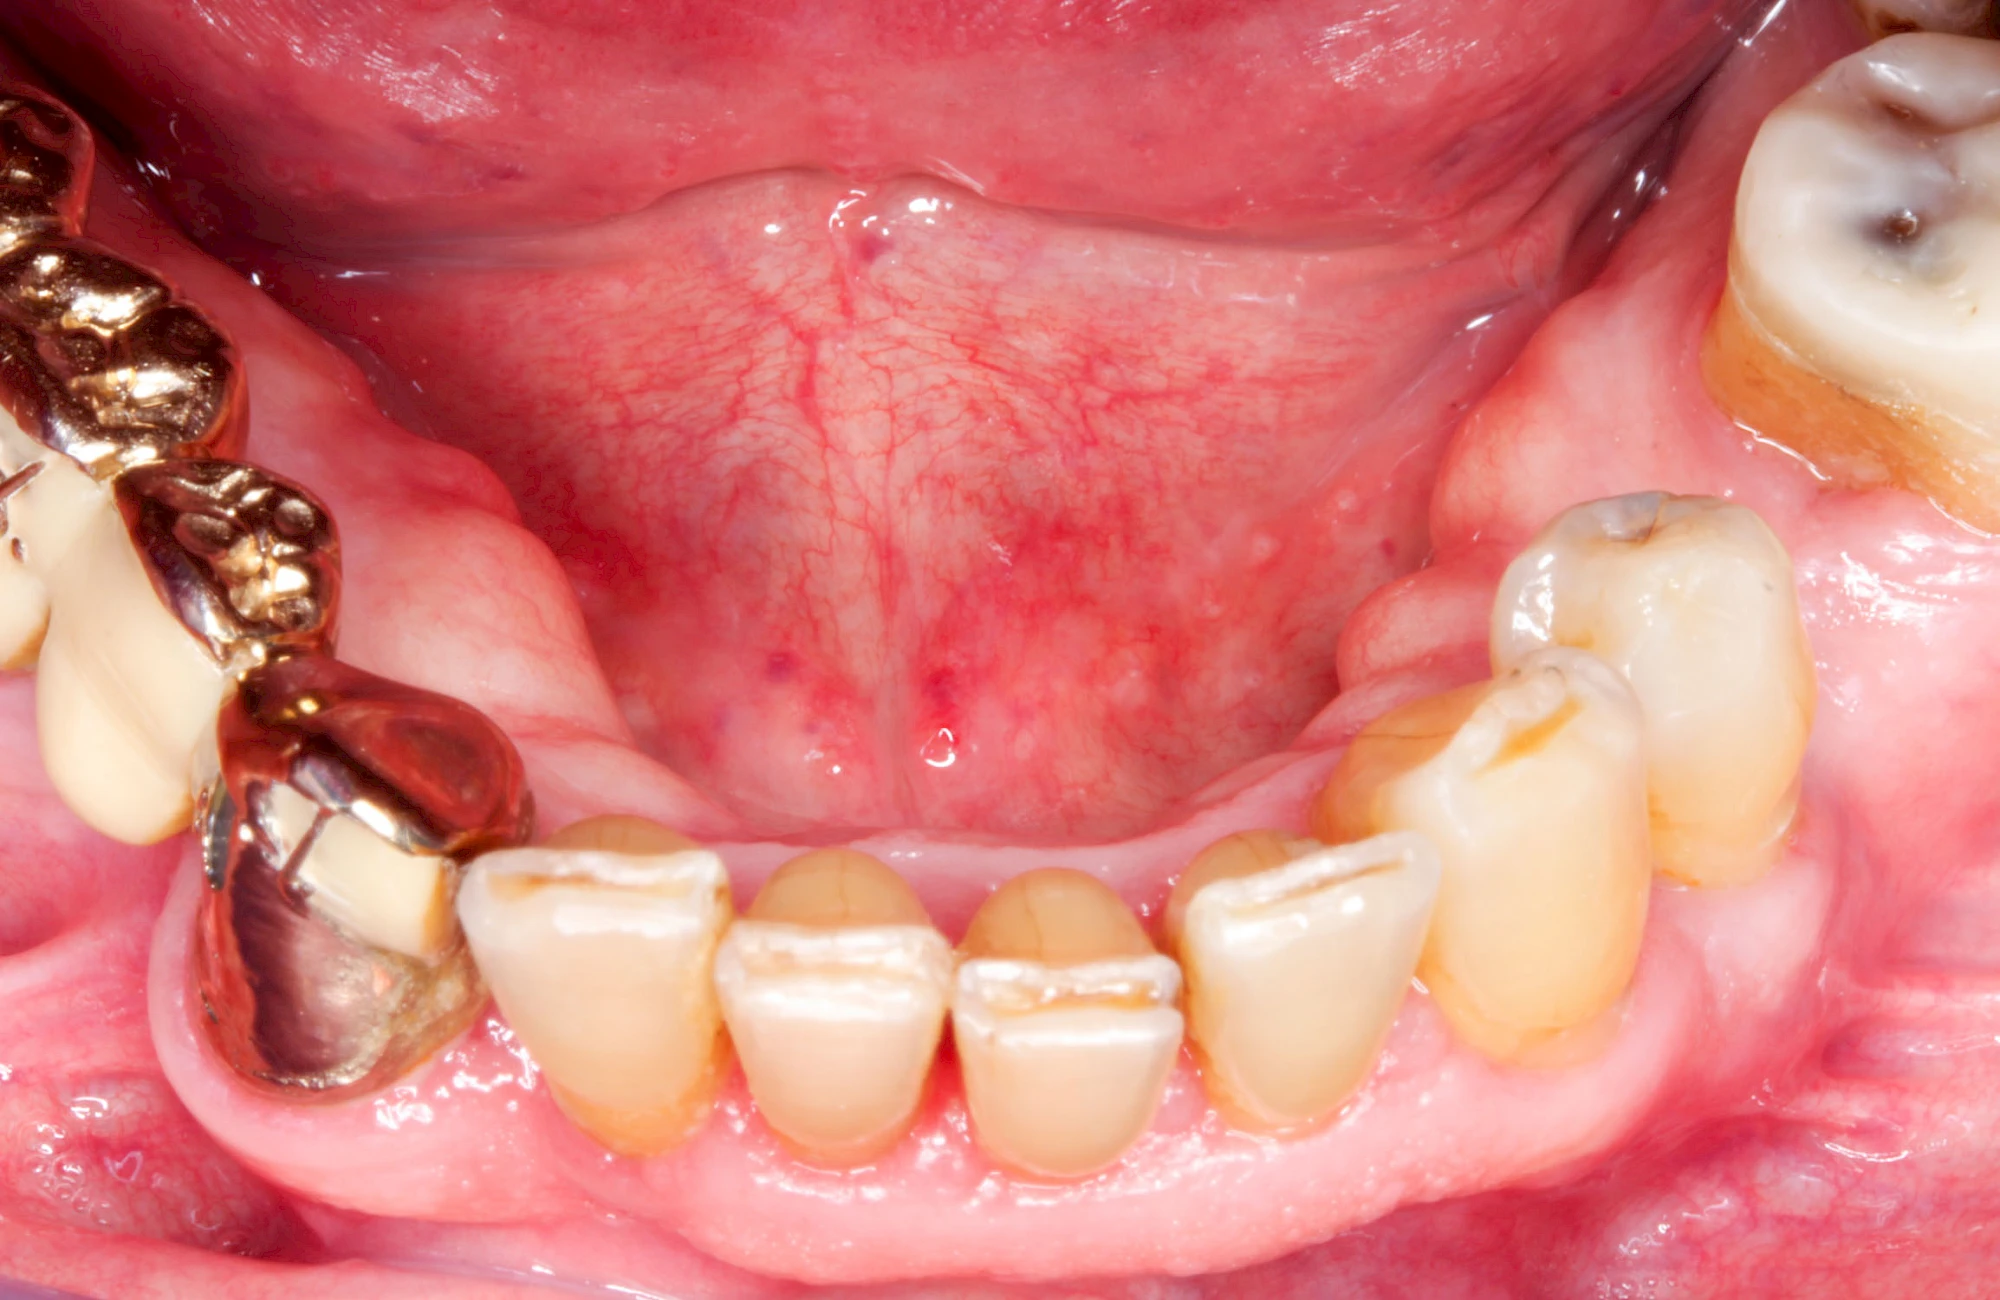

Gehen die Zähne verloren, baut häufig auch der Kieferknochen ab (Knochenschwund). Die Geschwindigkeit und das Ausmaß des Knochenschwundes ist von vielen Faktoren abhängig. Neben der genetischen Veranlagung spielen auch Überbelastungen in Folge, z. B. bei ständigem Knirschen oder Pressen, eine Rolle. Auch wenn Zahnprothesen Tag und Nacht getragen werden, kann die ständige Belastung der Schleimhäute und des Knochens den Knochenschwund beschleunigen.

In seltenen Fällen schwindet nur der Knochen, aber nicht die bedeckenden Schleimhäute. In diesen Fällen spricht man von einem sogenannten "Schlotterkamm".